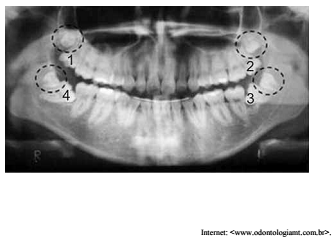

Paciente do sexo masculino de vinte e três anos de idade

compareceu ao consultório odontológico portando exames

radiográficos para avaliar a necessidade de fazer um tratamento.

A figura apresentada ilustra a radiografia panorâmica do paciente,

a qual mostra a presença de quatro dentes supranumerários retidos

(representados pelos círculos pontilhados) e terceiros molares

retidos (indicados pelos numerais 1, 2, 3 e 4).

Considerando esse caso clínico e tendo a figura como referência,

assinale a opção correta que corresponde aos procedimentos

cirúrgicos que devem ser adotados pelo odontólogo.